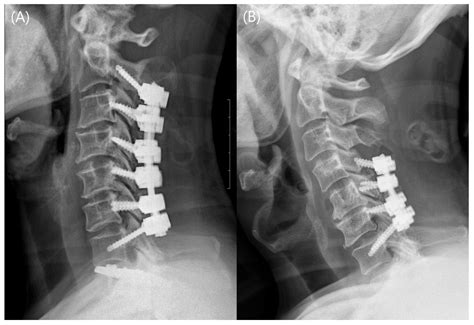

• Anterior Cervical Discectomy and Fusion (ACDF): This is the most common type of cervical fusion surgery. It involves accessing the spine from the front of the neck, removing the damaged disc, and inserting a bone graft or artificial disc to promote fusion.

• Consultation and Evaluation: Patients will undergo a thorough evaluation, including medical history, physical examination, and diagnostic tests such as X-rays, MRI, or CT scans.

• Fixation: Plates, screws, or other fixation devices may be used to stabilize the vertebrae and promote fusion.